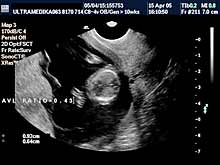

A) I trimestar do 14

nedelje gestacije

(3 meseca + 2 nedelje)

Indikacije za ultrazvučni pregled:

- Izostanak menstruacije, procena vitalnosti rane trudnoće,

procena materične i/ili postojanje vanmaterične trudnoće.

(Od 4-7 nedelje gestacije, ili prva 2 meseca od prvog dana zadnje

menstruacije).

- GENETSKI SONOGRAM (2 - 3 ½ meseca):

- Otkrivanje ultrazvučnih markera na postojanje hromozomskih

anomalija ploda (SKRINING na ANEUPLOIDIJE). Ovaj genetski sonogram

treba uraditi dva puta u intervalu od 9 do 14 nedelje gestacije uz

biohemijsku proveru iz krvi trudnice nakon tačne ultrazvučne procene

veličine ploda. Genetski sonogram sam isključuje oko 88% trizomija,

a udružen sa biohemiskim analizama se isključuje oko 98%

aneuploidija.

- Prva procena i otkrivanje krupnih anatomskih anomalija ploda

koje ne moraju pratiti hromozomske anomalije.

- Prva procena posteljične cirkuacije Broandband - CD

- Pregled materice i organa male karlice kao i organa abdomena

trudnice.